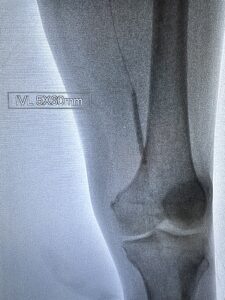

Υβριδική Αντιμετώπιση της Αρτηριακής Ισχαιμίας Share this post Share on FacebookShare on Facebook TweetShare on Twitter Share on LinkedInShare on LinkedIn